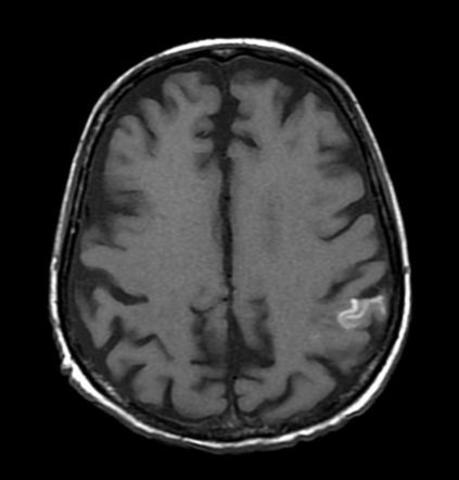

• Disposición anatómica de los vasos sanguíneos cerebrales

Disposición anatómica de los vasos sanguíneos cerebrales

Predispone el desarrollo de dos tipos de lesión: el infarto en divisoria de aguas y la necrosis laminar.

• Infarto en divisoria de aguas

Infarto en divisoria de aguas

Se localiza en zonas anatomicamente vulnerables situadas entre territorios superpuestos irrigados por las arterias cerebrales mayores (arterias media, anterior y posterior). Cuando hay disminución del flujo sanguineo, la irrigación sanguínea en estas zonas dismunuye en forma muy pronunciada. El restablecimiento del flujo sanguíneo se asocia con la recuperación funcional de áreas de la corteza irrigadas por las arterias cerebrales mayores.

• Necrosis Laminar

Necrosis Laminar

Se sitúa en regiones irrigadas por las arterias penetrantes. Un descenso brusco de la presión arterial reduce significativamente el flujo sanguíneo en las arterias penetrantes cortas que se encuentran en la S.gris de la corteza cerebral y que irrigan en la piamadre y forman una red capilar, esto produce una necrosis resultante de tipo laminar y afecta las capas más profundas de la corteza cerebral.